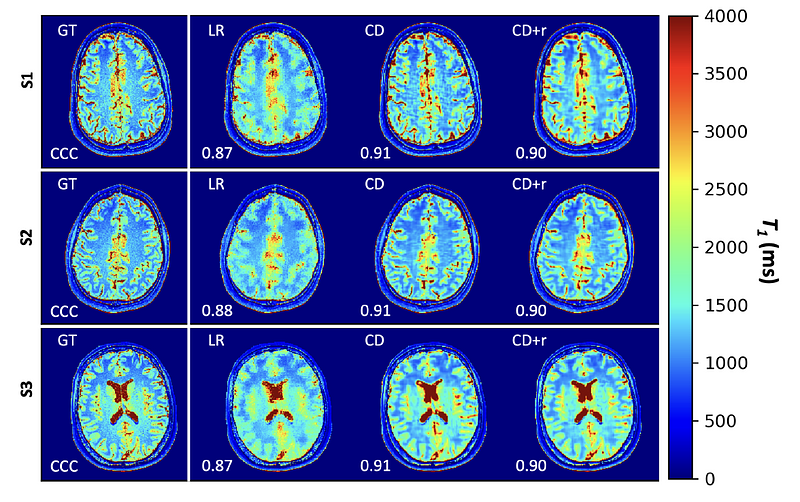

Results: Our method, CD+r, yielded reconstructions with SSIM>0.90 for acceleration factors as high as 12, bringing down the effective acquisition time from 50 minutes to approximately 4 minutes. We also found high agreement (CCC>0.90) between ground truth T1 maps and reconstruction-based T1 maps for the same acceleration factor.

Results of simultaneous T1 mapping. For each subject (row), the ground truth (GT) maps are at left, followed by maps from the locally low rank, non-regularized deep learning, and regularized deep learning recon (ours).